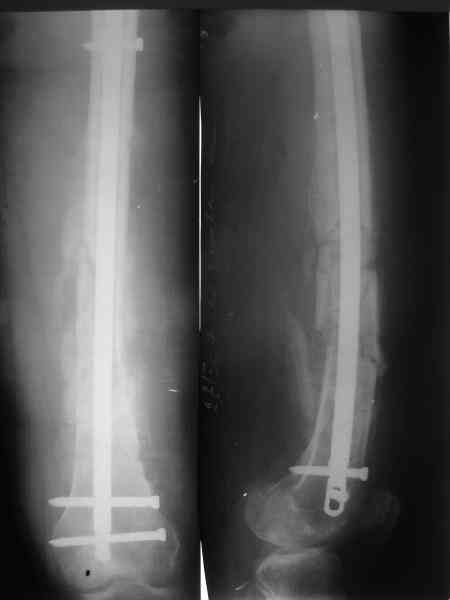

В мае 2007 года оперирована в Уральском НИИТО г. Екатеринбурга.

Выполнено: полузакрытое удаление пластины и винтов, IM блокируемый

остеосинтез.